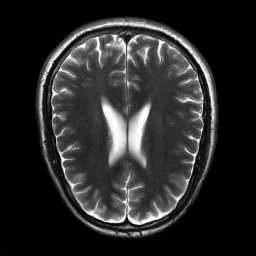

Generative adversarial networks are a kind of deep generative model with the potential to revolutionize biomedical imaging. This is because GANs have a learned capacity to draw whole-image variates from a lower-dimensional representation of an unknown, high-dimensional distribution that fully describes the input training images. The overarching problem with GANs in clinical applications is that there is not adequate or automatic means of assessing the diagnostic quality of images generated by GANs. In this work, we demonstrate several tests of the statistical accuracy of images output by two popular GAN architectures. We designed several stochastic object models (SOMs) of distinct features that can be recovered after generation by a trained GAN. Several of these features are high-order, algorithmic pixel-arrangement rules which are not readily expressed in covariance matrices. We designed and validated statistical classifiers to detect the known arrangement rules. We then tested the rates at which the different GANs correctly reproduced the rules under a variety of training scenarios and degrees of feature-class similarity. We found that ensembles of generated images can appear accurate visually, and correspond to low Frechet Inception Distance scores (FID), while not exhibiting the known spatial arrangements. Furthermore, GANs trained on a spectrum of distinct spatial orders did not respect the given prevalence of those orders in the training data. The main conclusion is that while low-order ensemble statistics are largely correct, there are numerous quantifiable errors per image that plausibly can affect subsequent use of the GAN-generated images.